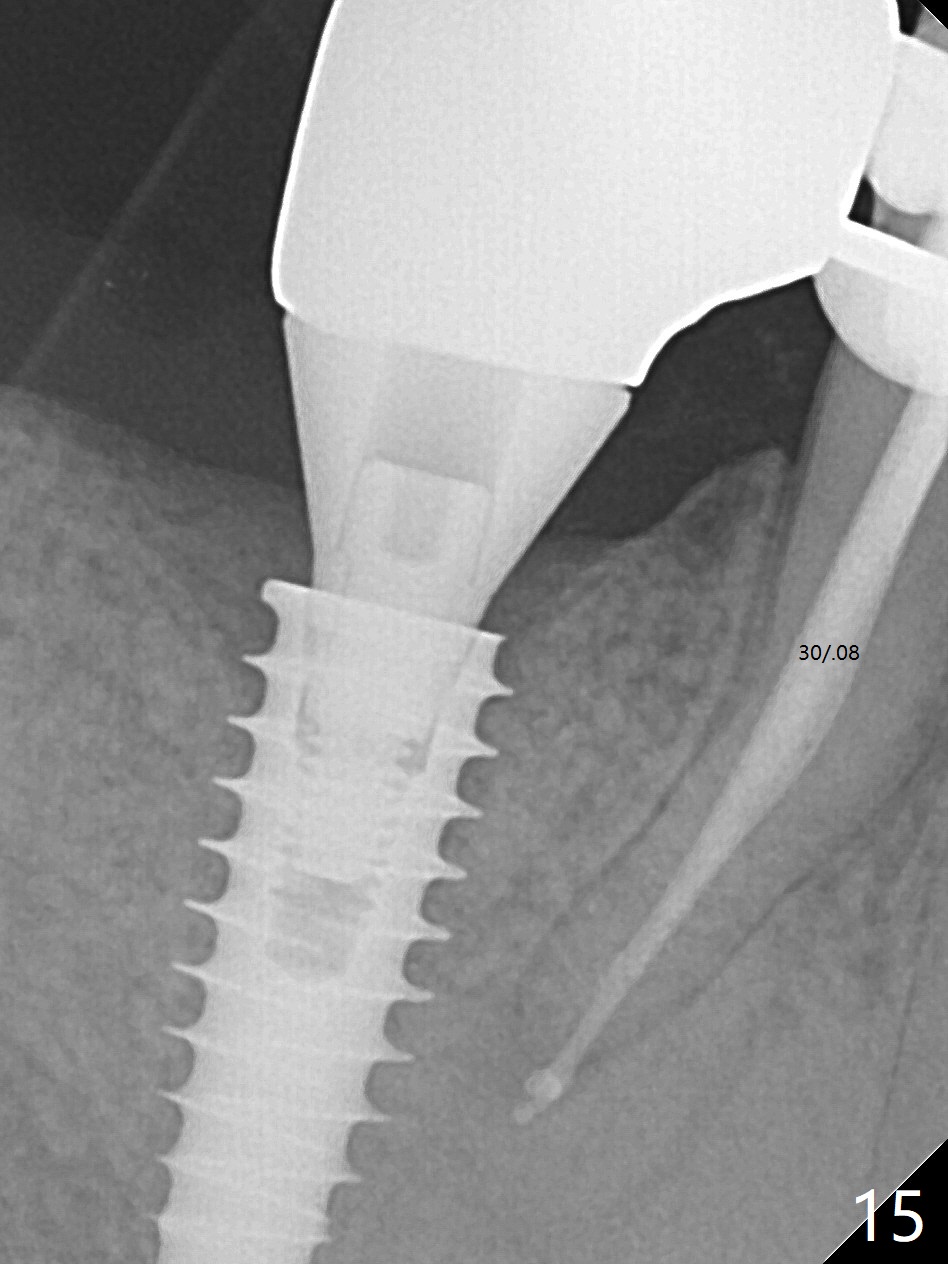

Bone graft seems to sink down and becomes denser 3 months postop (Fig.6 arrow). The bone continues being denser 5 months postop (Fig.7). There is periapical radiolucency of the tooth #29 (^). RCT is done (Fig.8). The pain persists 2 weeks postop (Fig.9,10). There is no missing canal (Fig.9). The apex is close to the implant (Fig.9 *). Apicoectomy will be performed if needed. It appears that the implant is also placed buccal (Fig.10 <) and/or the implant too large for the site. Therefore there should be a 2-3 mm buccal gap before and after implant placement. Separation and reflection of the buccal flap allows better visibility. The pain persists 1 month post RCT and 6 months post implant placement. RCT retreatment is initiated (Fig.11,12) with placement of Calcium Hydroxide paste after redebridement with 30/.04 rotary file at 23.5 mm (.5 mm longer than the earlier RCT, Fig.13). RCT retreatment finishes with apparent transportation and extrusion in 4 weeks (Fig.14,15), followed by apicoetomy (Fig.16,17) (20 days later)). Discomfort remains 2.5 months postop (Fig.18). Keep watching.